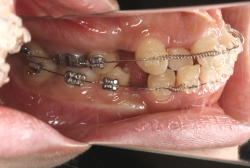

診断の結果、典型的なアングル2級1類の上顎前突です。上下歯列の正中の不一致も見られます。しかし、歯の大きさは平均値に近く、配列の凸凹がそれほど見られません。このまま放置すると、将来的には抜歯を伴う矯正治療を行う可能性が高くなりますが、このタイミングで適切な治療をすると、非抜歯治療が可能かもしれません。

矯正歯科医が着目するのは、奥歯の噛み合わせの位置関係です。前歯の位置にそれなりの差が生じていても、奥歯の位置が正しければそれほど重症という評価にはなりません。このケースの場合は、上下の第一大臼歯の位置関係は、直線的に一致しているタイプでした(矢印が一致)。混合歯列時期の奥歯の位置関係としては、ほぼ正常な状態といえますが、症状から言うと、上の奥歯をもっと後ろに下げてやることができれば、上顎歯列全体に余裕ができるので、凸凹も解消できるし、前歯の傾きを内向きに修正することもできると考えられました。しかしこのまま全体に永久歯が生えきってしまうと、上の前歯が出たままになってしまいますので、生え替わりが完了する前に大急ぎで奥歯を後ろに下げる必要があると判断しました。

こういう症状でもっとも効果があるのが、顎外固定装置と言って、お口の外部から奥歯に力をかける方法です。 写真の装置はネックバンドというタイプの装置です。この装置は取り外し式ですので、夜寝るときに毎日自分で取り付けて、寝ている間に少しずつ上の奥歯を後ろに下げていきます。この装置には、奥歯を後ろに下げる効果だけでなく、上顎の過剰な成長発育の抑制、下顎の成長促進作用があるとされており、上顎前突の症状にはいずれも有利な効果が期待できます。

ネックバンドを1年半使用して、上顎大臼歯が十分後ろに下がったところで、裏側にリンガルアーチという固定のワイヤーを取り付けて、新しく生じた隙間が狭くならないよう「保隙(ほげき)」という処置をして、永久歯が生えそろうまで待機中の様子です。配列全体に隙間が生じているのがお分かりいただけると思います。これだけの隙間が確保できていれば、抜歯をしなくても、あとで上の前歯を内側に理想的な角度で引っ込めることができます。このように完全に永久歯列になる前に、十分な隙間が確保できるかどうかが、非抜歯で矯正できるかどうかの分かれ目になります。